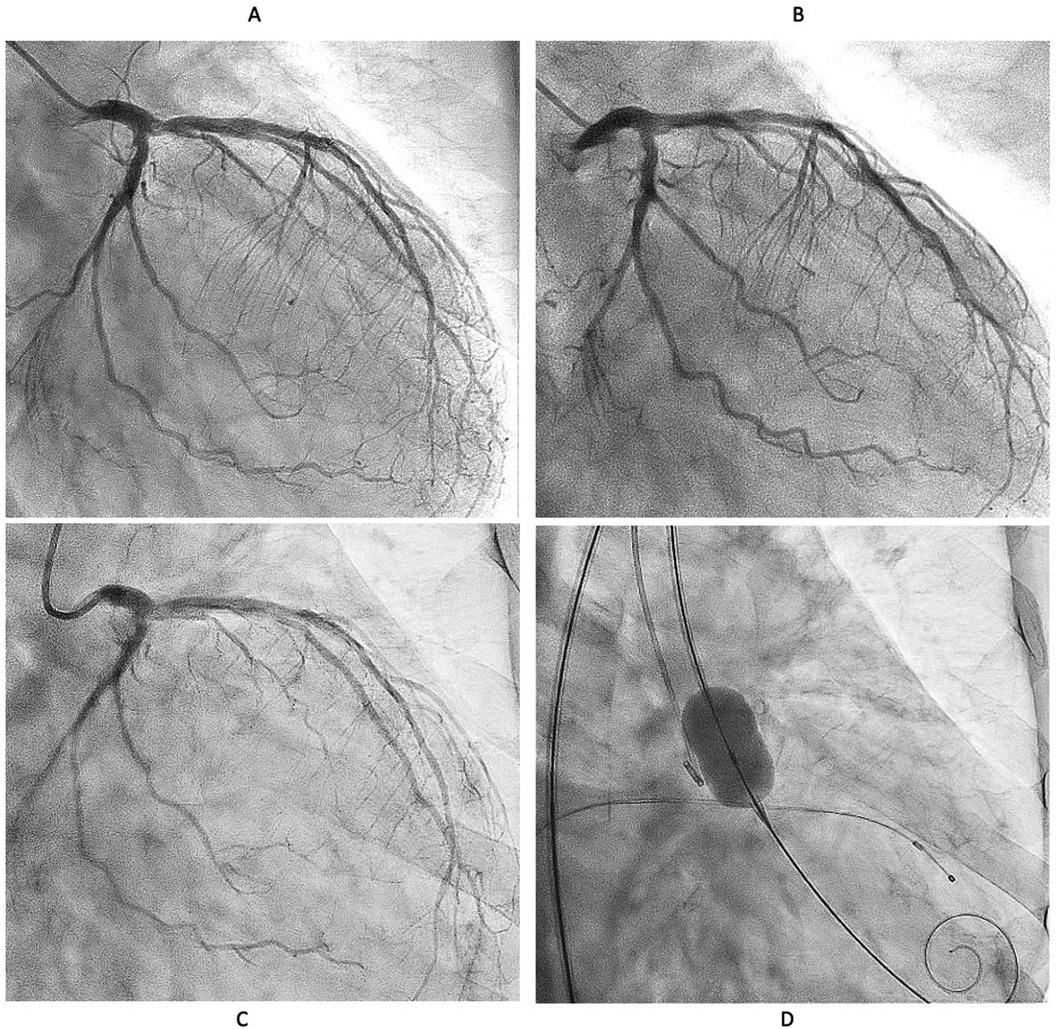

However, six months later, the symptoms recurred, and CAG revealed restenosis at the LCX (Figure 2A). Therefore, we proceeded with repeat PCI. The lesion appeared hazy on angiography, with small channels visible within the lesion. We selected an 8-French system, considering the possible need for a large-diameter Rotablator. IVUS showed that the lumen was filled with proliferative calcified tissue. While IVUS indicated features suggestive of a CN, it had already been treated six months earlier, so the proliferative CN tissue was assumed to be not very hard. Therefore, we attempted to remove the CN using directional coronary atherectomy (DCA). We selected a medium-size ATHEROCUT catheter (NIPRO, Japan) and performed a total of 31 cuts at a maximum pressure of 40 psi. After removing a total of 12.2 mg of CN tissue with DCA, the lumen was significantly enlarged (Figure 2B). Next, the lesion was dilated using a CB 3.25 mm, which was a quarter size larger than the previous one, followed by a SeQuent Please 3.5 × 20 mm (Figures 2C,D). The final angiogram showed a no residual stenosis without any complications (Figure 2E). However, 6 months later, the symptoms recurred, and CAG showed restenosis again with irregular channel (Figure 3A). Despite recurrent restenosis of the lesion, we decided to perform repeat PCI for this lesion because the patient was at high risk for bypass surgery due to hemodialysis. This time, we also chose an 8Fr system. We needed to take a different approach from the previous two procedures. OFDI revealed a very eccentric lumen with an irregular surface. Both eruptive and non-eruptive CNs were present in the same lesion.

Series of medical images showing coronary angiography and histological analysis. Panel A shows a vessel with minimal lumen area (MLA) of 1.72 mm². Panel B displays the vessel after directional coronary atherectomy (DCA) with MLA of 7.22 mm². Panels C and D show stages of the procedure. Panel E presents the final MLA of 7.70 mm². Panels F and F' depict histological slides highlighting fibrin content.

Figure 2. Second intervention for LCX ostial lesion (white arrow). (A) Angiography and IVUS showed restenosis with irregular surface. Lumen was filled by proliferative calcified tissue that was like non-eruptive CN. (B) Directional coronary atherectomy (DCA) was performed to reduce the CN using Atherocut (NIPRO), and then lumen was much gained. (C,D) The lesion was dilated using Wolverine cutting balloon 3.25 × 10 mm, which is one-quarter size up from previous one, followed by SeQuent Please 3.5 × 20 mm. (E) Final angiogram and IVUS showed good result with more circular lumen compared to the first intervention (white arrow). Low- (F) and high- (F′) power images of the tissue collected through directional coronary atherectomy revealed the calcified nodule with fibrin deposition (red arrow). Abbreviations are as defined in Figure 1.

We decided to perform rotational atherectomy using a large burr. First, a 1.75 mm burr was used. OFDI showed an enlarged lumen surrounded by residual CN. Subsequently, a 2.25 mm burr was then used for further debulking. A repeat OFDI then demonstrated further lumen enlargement without evidence of vessel wall injury (Figures 3B,C). Then, the lesion was dilated using a CB 3.75 × 10 mm, which is a quarter size up from previous PCI, followed by a SeQuent Please 3.5 × 25 mm. Final angiogram showed no residual stenosis without any complication (Figures 3D–F). Six months later, the ostium of the left anterior descending artery (LAD) was treated, with no restenosis the observed in the CX (Figure 4A). At one-year follow-up, there was no restenosis in either the CX and LAD ostium (Figure 4B). Four years later, the complained of chest pain again, so CAG was performed. However, the CAG revealed no restenosis at CX, even after 4 years (Figure 4C). He had severe aortic valve stenosis (AS) but was in the terminal stage of colon cancer. Therefore, we performed balloon aortic valvuloplasty for the severe AS (Figure 4D). We ultimately succeeded in overcoming the CNs in this patient.

Four-panel angiogram images labeled A, B, C, and D. Each panel shows different views of coronary arteries. Panels A, B, and C depict the arterial branches with varying levels of visibility and contrast. Panel D displays a balloon catheter within a coronary artery, indicating an interventional procedure.

Figure 4. Serial angiographical follow up. (A) Angiography at 6 months showed no restenosis. Left anterior descending (LAD) ostial lesion was treated Rotablator followed by DCB. (B) No restenosis was observed at one year both CX and LAD. (C) Angiography revealed no restenosis even after 4 years. (D) Severe Aortic valve stenosis was treated with balloon aortic valvuloplasty instead of transcatheter aortic valve implantation because the patient was in the terminal stage of colon cancer.